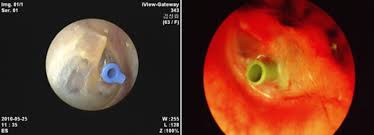

중이염은 귀 내부의 중이에 염증이 생기는 상태를 의미합니다. 일반적으로 상기도 감염이 원인이 되며, 감기나 비염을 앓고 난 후 중이염에 걸리는 경우가 많습니다. 중이염은 크게 급성 중이염과 만성 중이염으로 나뉘며, 각각의 증상과 관리 방법이 다릅니다. 급성 중이염은 통증과 발열이 동반되며, 만성 중이염은 염증이 지속적으로 반복될 수 있습니다. 특히 어린이에게서 중이염이 자주 발생하는 이유는 이관의 구조가 성인보다 짧고 수평적이기 때문에 병원균이 쉽게 침투할 수 있기 때문입니다.

중이염은 귀에만 국한된 질환이 아니라, 호흡기 질환과 밀접한 연관이 있습니다. 코와 귀는 이관이라는 통로로 연결되어 있기 때문에 비염이나 감기 등 상기도 질환이 있을 때 중이염이 발생할 위험이 높아집니다. 이관이 막히면 중이의 압력이 불균형해져 염증이 발생할 수 있으며, 그 결과 귀 안에 염증성 삼출액이 고이게 되어 중이염으로 이어질 수 있습니다. 따라서 호흡기 건강을 관리하는 것이 중이염 예방에 효과적입니다.